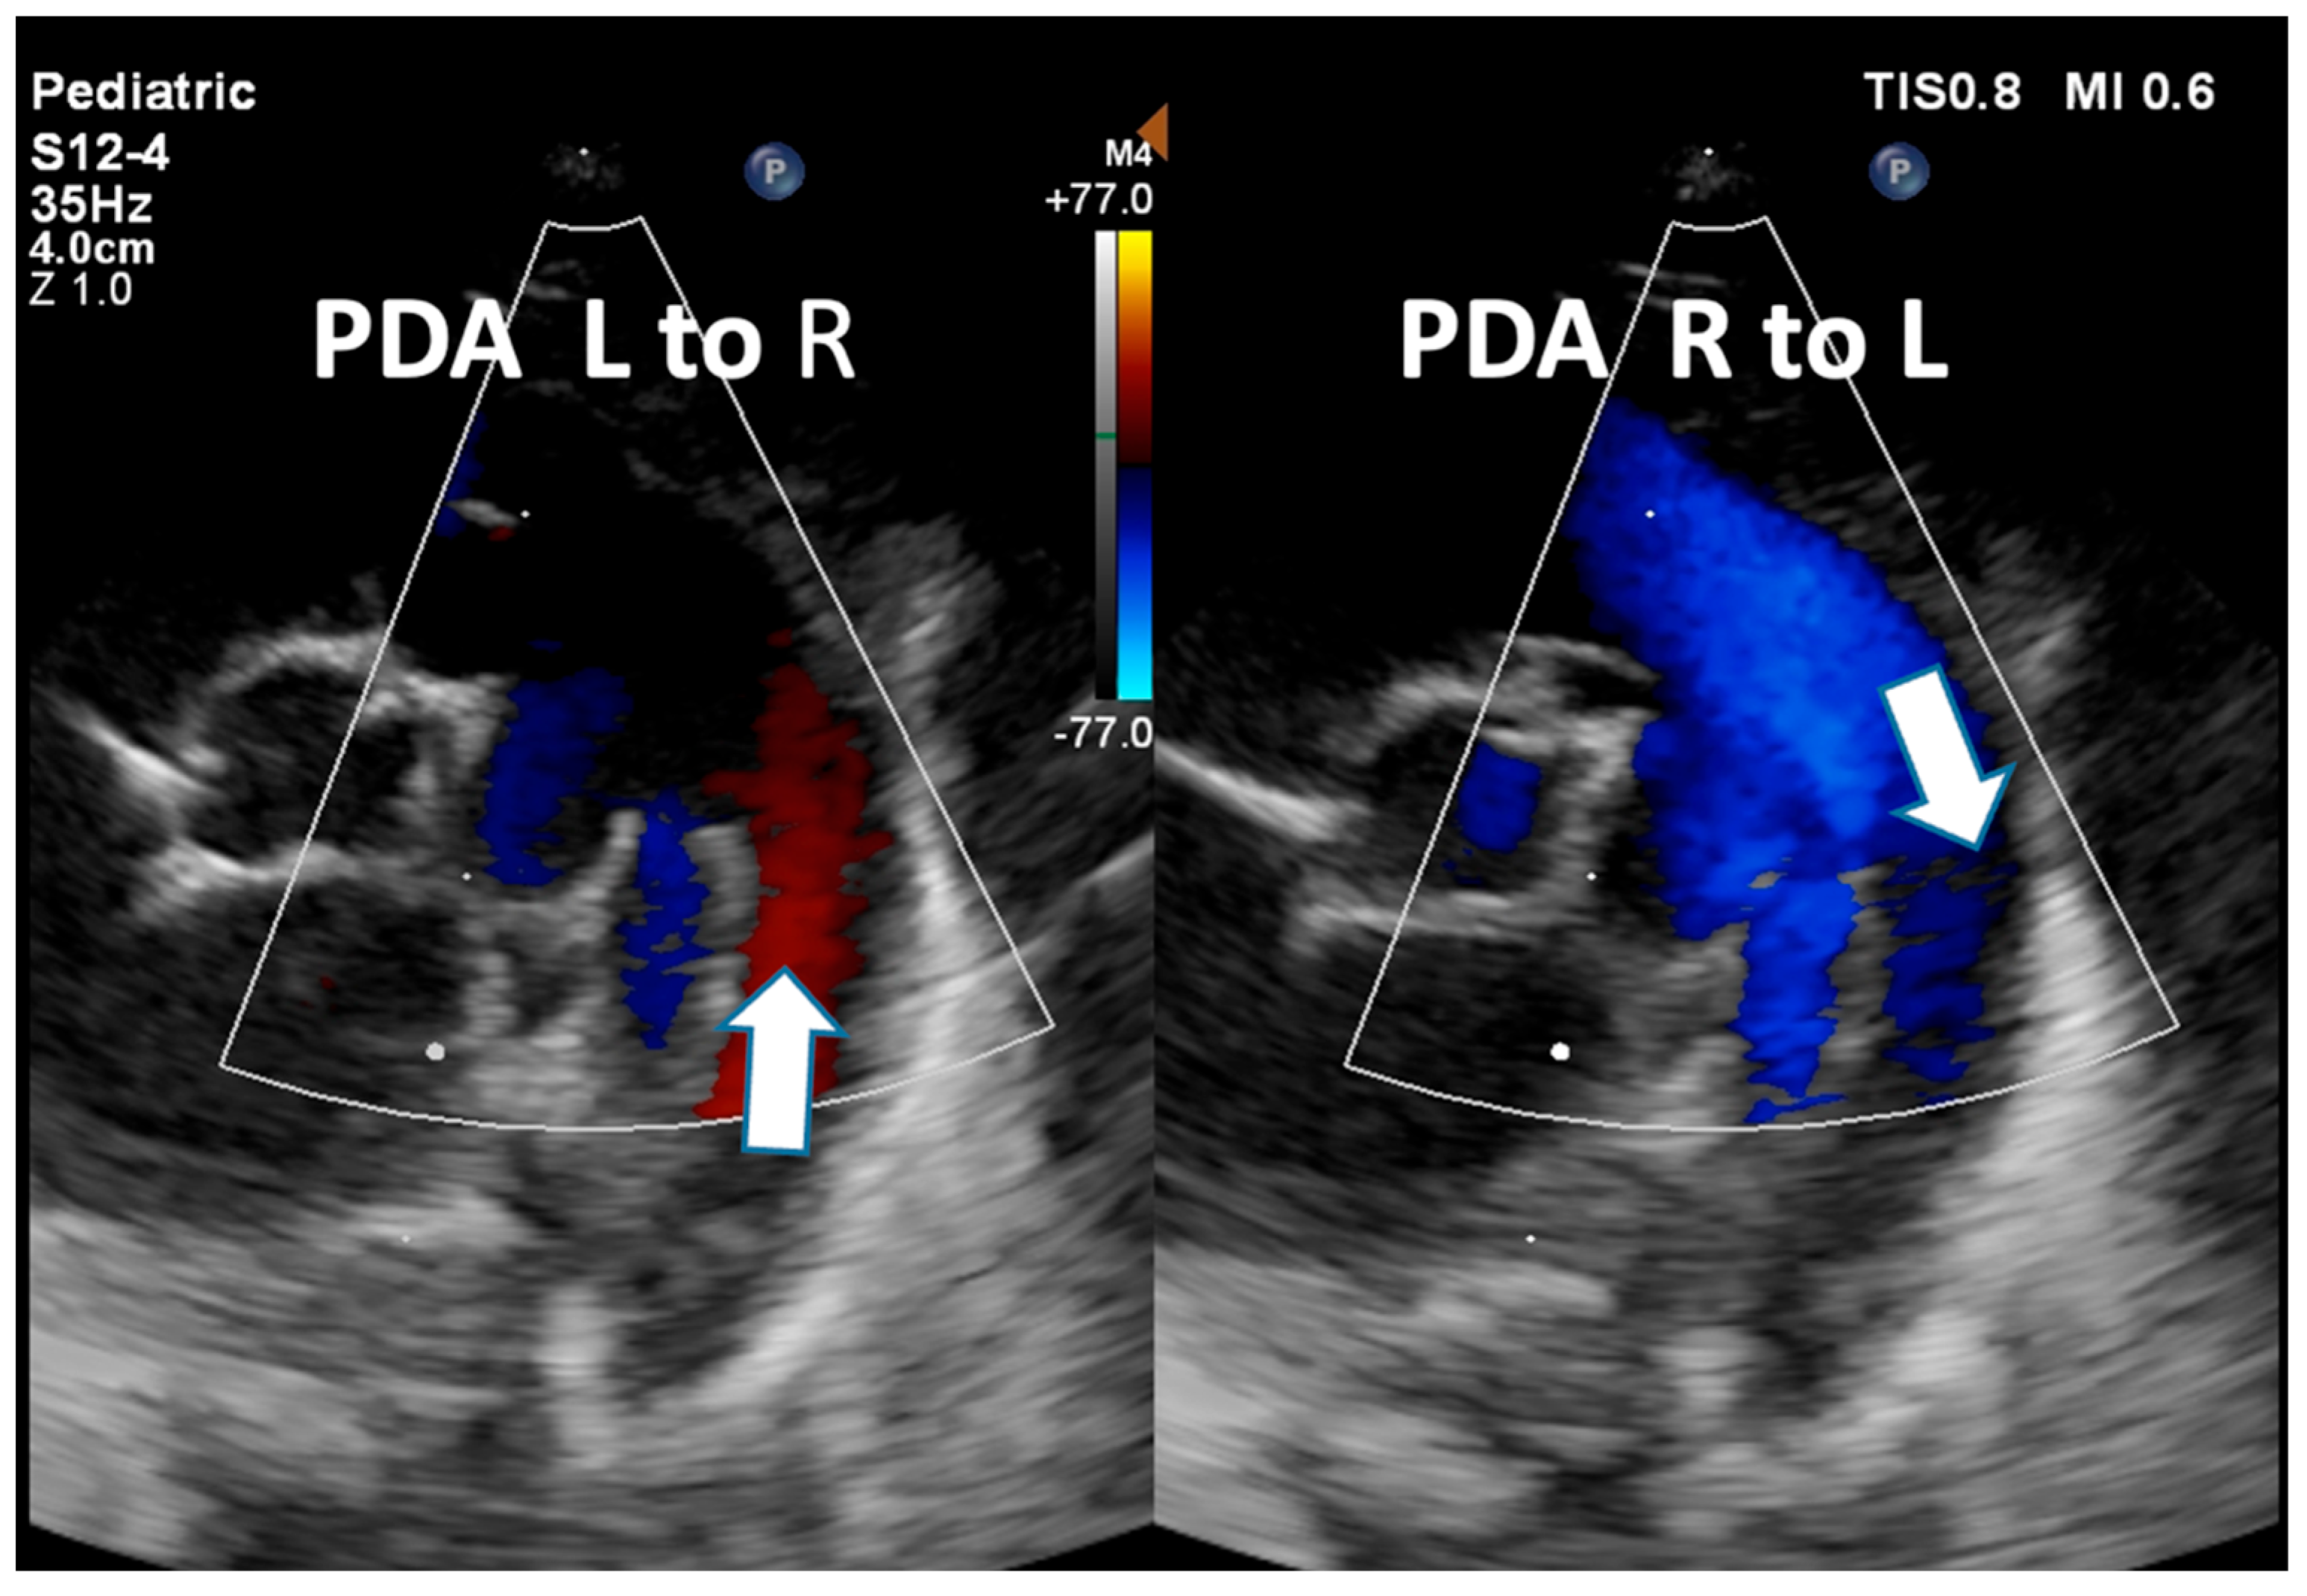

| Detection of Shunt | Identification and assessment of flow through the patent foramen ovale (PFO) and ductus arteriosus (PDA) | Indicates the presence and nature of pathological flow: left-to-right, bidirectional (often in moderate PPHN), or right-to-left (in very severe PPHN) |